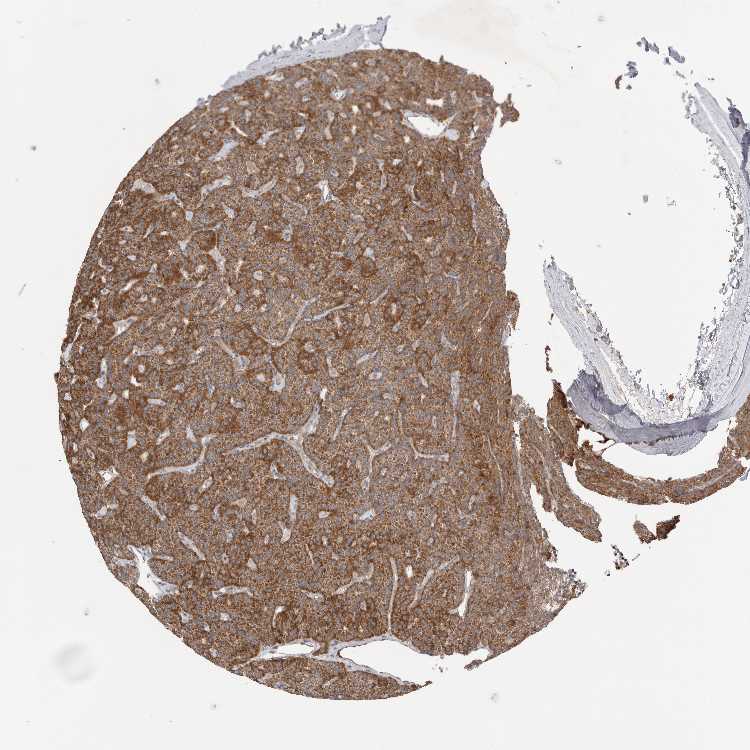

PARATHYROID GLAND - Antibody stainingi

Antibody staining in the annotated cell types in the current human tissue is reported as not detected, low, medium, or high, based on conventional immunohistochemistry profiling in selected tissues. This score is based on the combination of the staining intensity and fraction of stained cells.

Each image is clickable and will lead to virtual microscopy that enables deeper exploration of all samples and also displays staining intensity scores, fraction scores and subcellular localization as well as patient and tissue information for each sample.

Antibody HPA024823

Glandular cells High